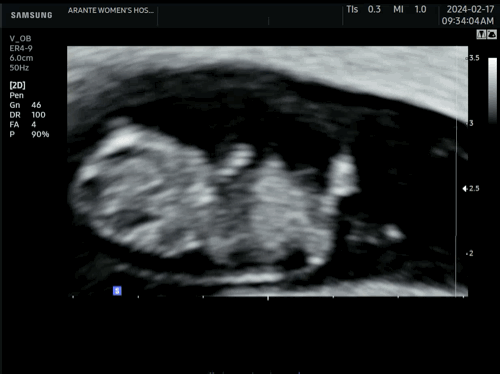

8주6일 너무 귀여운 쩰리곰

원래 수요일 병원가는건데, 배꼽 왼쪽 대각선 아래가 밤만 되면 찌릿? 바늘로 찌르듯 순간적인 통증이 이틀 째 있어서 걱정되어 병원 다녀왔어요! 원장쌤이 애기는 더 밑에 있어서 전혀 영향이 없고, 아마 아기집이 커지면서 주위 장기를 건드려 순간적으로 장이 아픈거일수도 있다고 하네요! 저 같은 분 참고하세요 ㅠㅠ 검색해보니 중기 산모들은 찌릿 통증이 많은데 .. 초기는 잘 없어서 걱정되었거든요. 아기는 8주6일 정상크기, 정상 심박수라고 하셨고 쩰리곰을 어쩜 이렇게 예쁘게 보여줄 수 있냐며 다같이 웃었네요 ㅎㅎ 아침부터 혼자 꼼지락거리며 놀고 있는게 너무 귀여웠어요 >.< 젤리곰 젤리곰하는데 다 이유가 있네요~ 쩰리곰 남기기 꼭 성공하세요!!!!